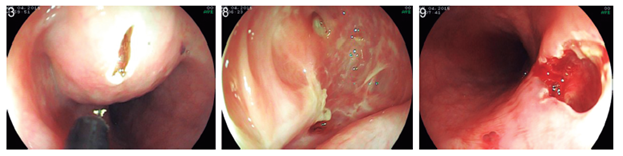

Ante los hallazgos que apoyaron el diagnóstico de quiste de duplicación sin malignización, se procedió a realizar una marsupialización del quiste bajo anestesia general en una sección de la pared luminal del mismo con electrobisturí de punta endoscópico. Se realizó un corte de 20 mm sobre el cénit de la lesión luminal con disección por pasos hasta la submucosa; se logró el completo drenaje de la lesión y su inspección endoscópica completa, y se encontró una cavidad ciega, recubierta por un epitelio pálido, sin características de malignidad (Figura 3).

La paciente evolucionó satisfactoriamente con dolor retroesternal como el único síntoma posterior al procedimiento, que cedió con los analgésicos comunes en las primeras 24 horas. Se inició una prueba de tolerancia oral en ese momento, sin presentar disfagia residual.

El control endosonográfico se llevó a cabo hacia el cuarto día posterior al procedimiento y se encontró un colapso completo de la lesión (Figura 4 A), asociado con una comunicación total con la luz esofágica en ausencia de residuos alimentarios (Figura 4 B).